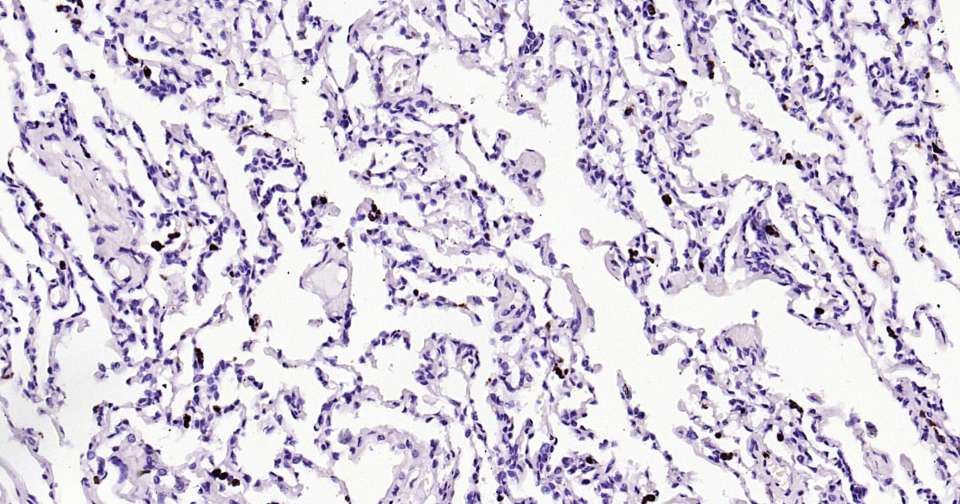

Immunohistochemical analysis of paraffin embedded human lung tissue slide using IHC0388H (Human Granzyme B Kit).